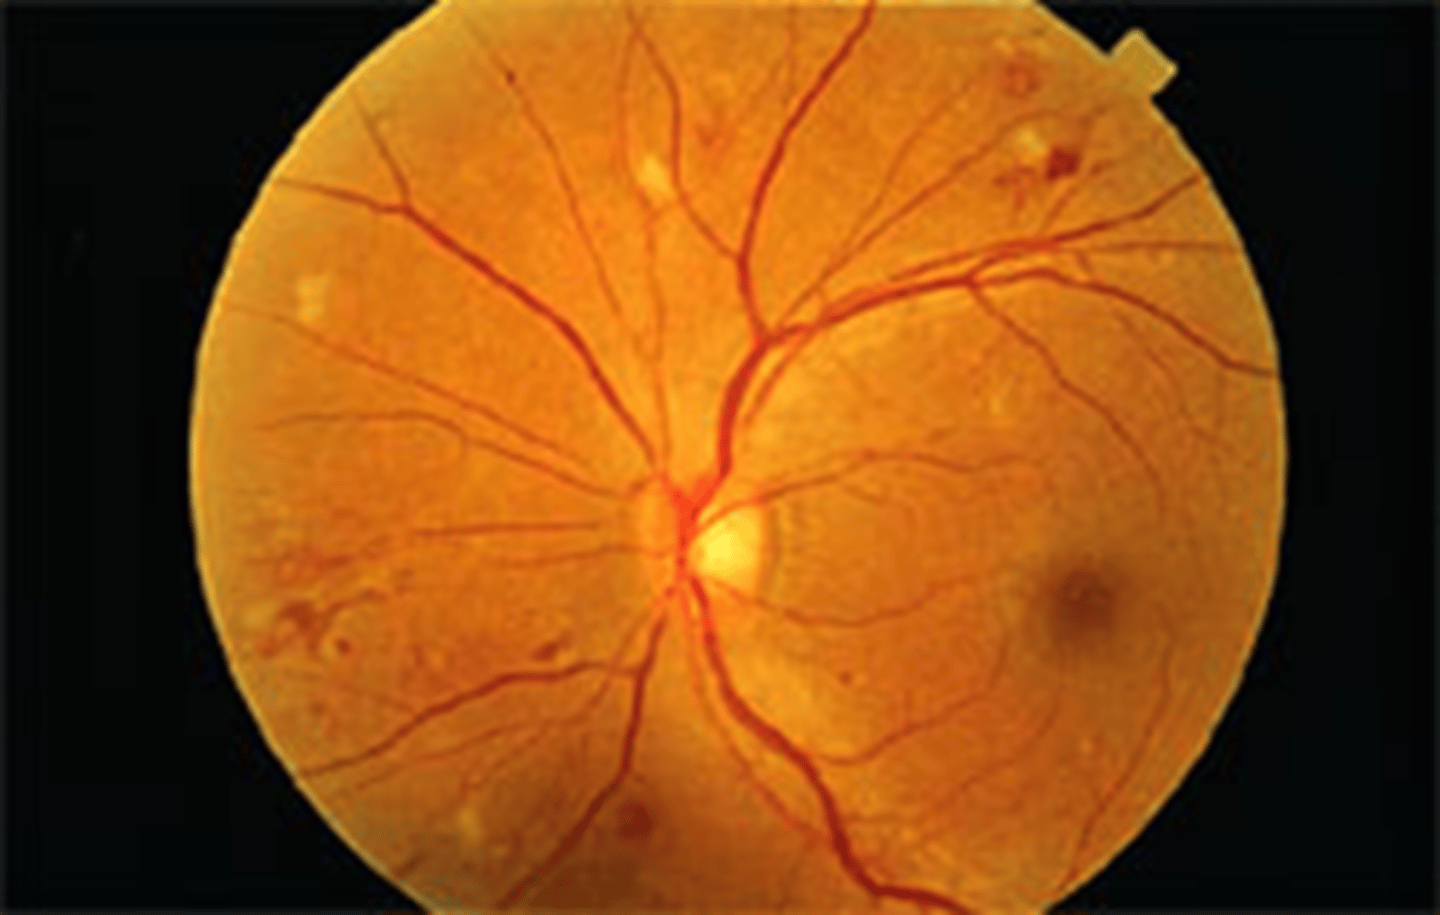

Keith-Wagener-Barker grade 4

what is this called

what is it most commonly associated with

where do exudates form (which layer)

hypertensive encephalopathy/malignant HTN: most commonly associated with acute, severe HTN

Optic nerve head edema, macular edema, venous engorgement and arteriolar constriction

rapid rise in BP damages the small vessel endothelium. Lipid exudates in the outer plexiform layer form a radiating pattern called a macular star